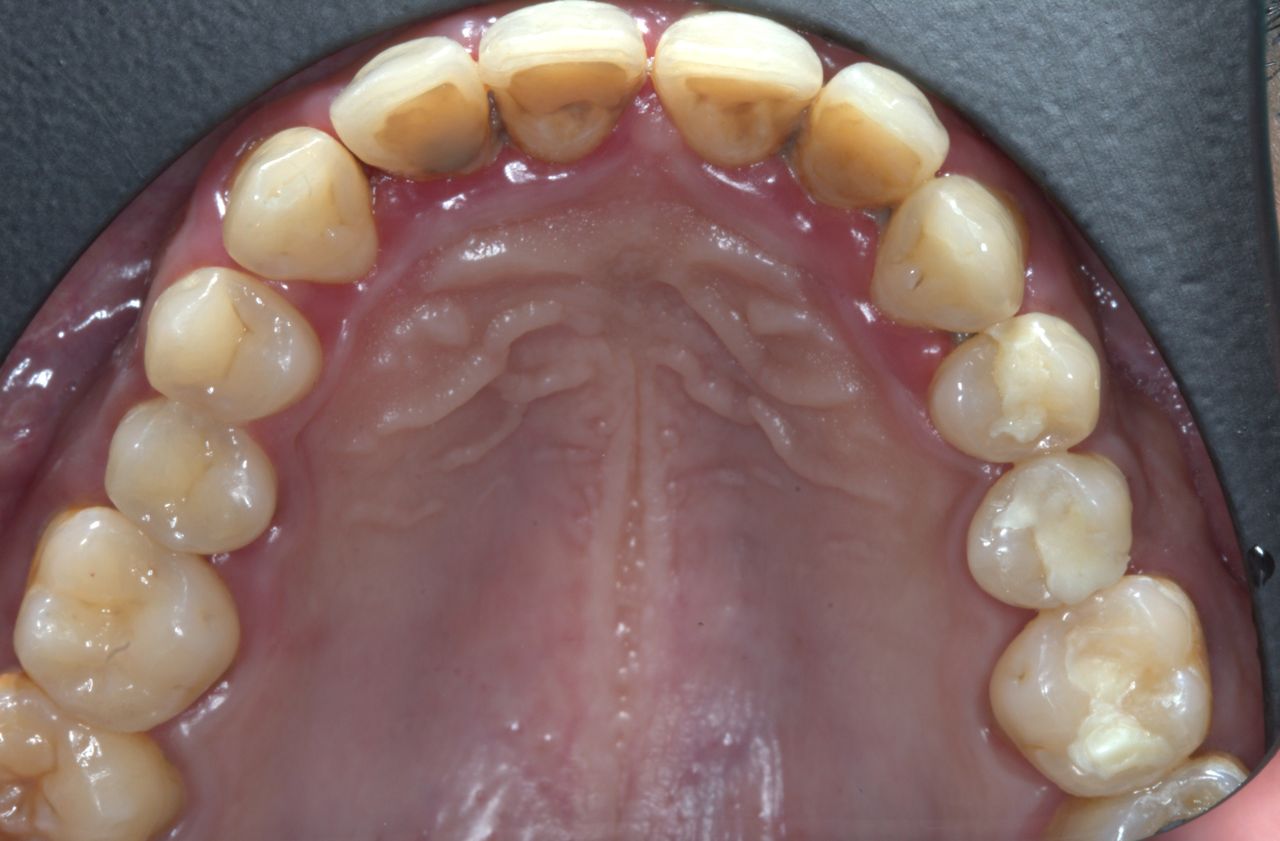

Fotos y videos

¿Que es un Implante Dental?

- Es un aditamento con forma de tornillo elaborado de titanio o de zirconio, que se inserta en el hueso a través de una pequeña cirugía, hasta que se osteointegre con el hueso y se coloque un provisional y posteriormente una corona definitiva.

-La ventaja de los Implantes Dentales es que sustituyen a los dientes o muelas perdidos sin que se tenga que desgastar los dientes adyacentes para un puente fijo.